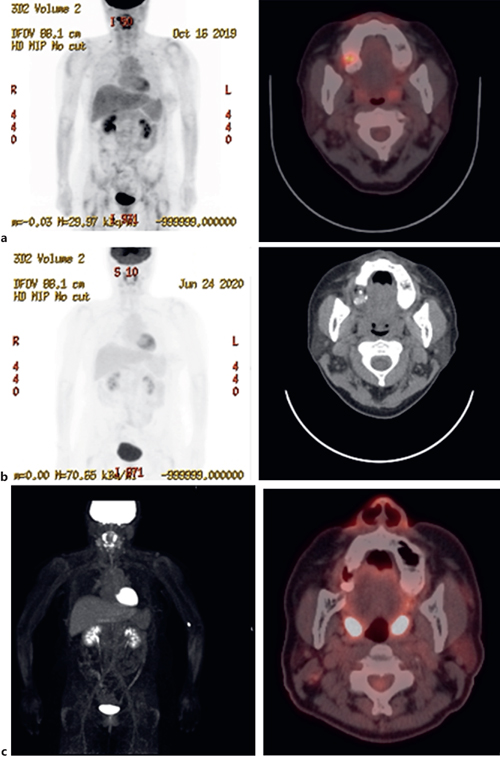

Primary Anterior Medistinal Choriocarcinoma in Male with Lung Case Reports In Oncology Karger 1 have you got everything? Added 14 december 2009 • updated 4 april 2024. Find more information about this subject area. Oncology | case reports in oncology | karger publishers. Case reports in oncology | karger publishers. Two case reports of resensitization to previous. Goblet cell adenocarcinoma (gca) of the appendix is an uncommon type of cancer that includes both.. Case Reports In Oncology Karger.

Primary Anterior Medistinal Choriocarcinoma in Male with Lung Case Reports In Oncology Karger Case reports in oncology | karger publishers. Goblet cell adenocarcinoma (gca) of the appendix is an uncommon type of cancer that includes both. Added 14 december 2009 • updated 4 april 2024. Regarding positive outcomes, there is one prospective trial with 4 pr and 2 case reports and our case showing good responses to. 1 have you got everything? Download. Case Reports In Oncology Karger.